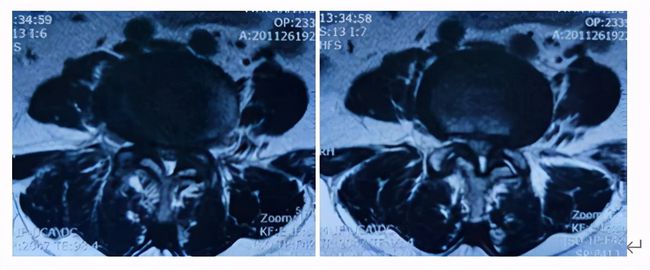

近期,邵女士前往上海交通大学医学院附属同仁医院脊柱外科就医,X线检查,腰4椎体轻度滑脱并有退变性侧弯,MR检查提示椎间盘突出,椎管明显狭窄,黄韧带肥厚、硬膜囊及神经根受压,诊断为:腰椎滑脱伴椎管狭窄症。

手术团队充分讨论,患者诊断明确,需手术解除椎管狭窄及恢复腰椎稳定。传统开放手术可以解决问题,但创伤较大,出血会较多,同时患者身体较差,存在一定风险。与患者沟通后,邵女士希望能微创手术治疗,最后决定行微创OLIF+内镜手术

本病例患者L3/4存在腰椎滑脱、椎间隙高度丢失;但L4/5椎间隙高度丢失不明显,所以选择了L3/4、L4/5两个节段的OLIF同是进行L4/5的内镜手术(OLIF+内镜),充分的结合了两种术式的优缺点,是间接减压与直接减压的完美结合。所以对于严重的椎管狭窄或滑脱也是可以采用微创的方式来解决的。目前国内开展此类微创手术鲜有报道。